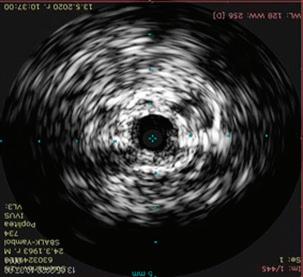

62 РЕТРОГРАДНА ПЕРКУТАННА

Лактазна неустойчивост. Състоянието (хиполактазия) е най-често срещаната физиоло -

гична причина за LI. Макар